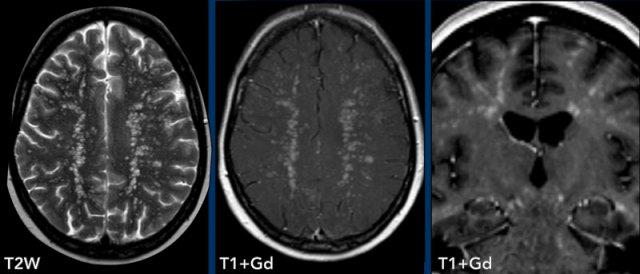

Các hình ảnh này của bệnh nhân 63 tuổi.

Hình ảnh

CT cho thấy tổn thương tăng tỷ trọng quanh não thất kèm phù não xung quanh.

Trên chuỗi xung T2W, tổn thương có tỷ trọng tương đối thấp. Tổn thương ngấm thuốc đồng nhất với nhiều tổn thương ngấm thuốc quanh não thất.

Tỷ trọng trên CT và phân bố tổn thương gợi ý mạnh đến u lympho.